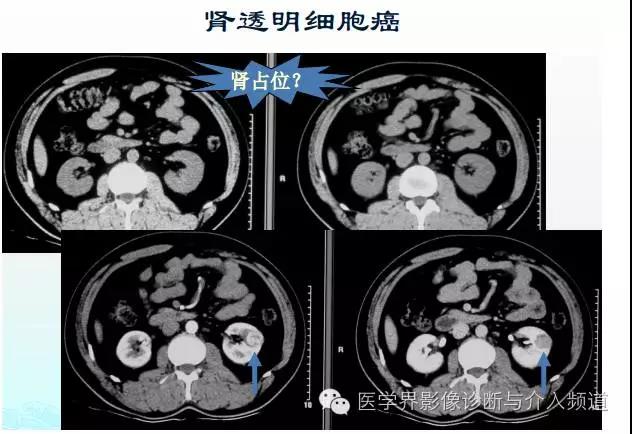

图2

图2是一个双肾平扫病例,CT平扫看到的是正常图像,使用增强CT后,左肾有一个明显的圆形强化灶,动脉期有明显的高密度,静脉期密度明显减低,增强显示该病的特点是“快进快出”,可判断患者为透明细胞癌。